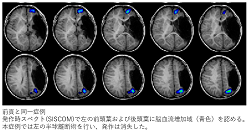

3-2. 結果: 術前評価

図3

• 発作症状:発作が記録された10例中の8例で側方徴候あり。

• 発作間欠期脳波:11例中5例で両側性で多焦点性のてんかん性放電がみられた。

• 発作時脳波:発作が記録された10例中の6例で発作の起始側は判定困難であった。

• 発作時スペクトを行った9例中の8例で一側性の高灌流がみられた。

• FDG-PETは機能低下域の検出に有用であった。

• 頭蓋内脳波をおこなった症例はなかった。